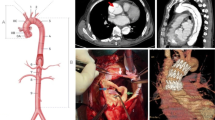

There are several surgical approaches for Type A aortic dissection. Approaches for dissection in the aortic root and ascending aorta include: replacement of the ascending aorta and aortic valve, combined replacement using a valved-conduit (Bentall procedure in Fig. 3a),18,19 and valve-sparing aortic root surgery (Figs. 3b, 3c, and 3d) involving coronary arterial re-implantation.20,21 Valve-sparing aortic root repair comprises remodelling of the native aortic valve and root into neo-aortic sinuses (Yacoub procedure in Fig. 3b),22 re-suspension of the aortic valve within the tubular ascending aortic graft (David procedure in Fig. 3c),23 or integration of both techniques. Recent evidence suggests that integration of remodelling and re-suspension (Fig. 3d) may provide additional support for obtaining stable root dimensions and aortic valve competency.24-26

Aortic root surgery (a, b, c, & d) and arch procedures (e, f, & g) for Type A aortic dissection. (a) The Bentall procedure involves replacement of the ascending aorta, root, and aortic valve with a valved-conduit. (b) The Yacoub procedure involves remodelling of the aortic root and sinuses with preservation of the native aortic valve (AV). (c) In the David procedure, there is replacement of the aortic root, re-suspension of the native AV within the tube graft, and reinforcement with sub-commissural annuloplasty. (d) A new technique integrating both remodelling (Yacoub) and re-suspension with sub-commissural annuloplasty (David). (e) Hemiarch repair. (f) Total arch replacement with Carrel patch. (g) Total arch replacement with branched graft anastomosis to individual brachiocephalic vessels and elephant trunk prosthesis

Surgery to the aortic arch depends on whether there is dissection in the transverse arch and the brachiocephalic vessels.27 In the absence of involvement in the distal arch and brachiocephalic vessels, a hemiarch repair (Fig. 3e) is performed. A total arch replacement is necessary when the intimal tear occurs in the transverse arch (Carrel patch in Fig. 3f) and between the brachiocephalic vessels (branched graft in Fig. 3g).28

Recent advances in surgical technique involve use of a trifurcated graft (Fig. 4a), which is perfused intraoperatively by cannulation of the right axillary artery.29 This novel technique enables cerebral perfusion to be maintained and is known as “branch-first” aortic arch replacement.30 It involves end-to-end anastomosis of the three brachiocephalic vessels to the trifurcated graft during sequential de-branching and replacement of the diseased aortic arch (Fig. 4b). Since cerebral perfusion is almost uninterrupted, the need for deep hypothermic circulatory arrest and associated complications can be obviated.29-31

The trifurcated graft in aortic arch replacement and hybrid arch procedure. (a) The trifurcated graft. (b) The “branch-first” aortic arch replacement enables continuous perfusion of the brain and upper body using a trifurcated graft. Sequential anastomoses of the three brachiocephalic vessels to the three limbs of the graft provide almost uninterrupted cerebral perfusion as the diseased arch is debranched and replaced. This trifurcated graft receives oxygenated blood via the right axillary artery (Ax). The lower body is perfused by retrograde flow of blood from a cannula placed in the femoral artery. Since cerebral perfusion is almost uninterrupted, the need for deep hypothermic circulatory arrest and the associated complications can be obviated. IA = innominate artery; RCC = right common carotid artery; LCC = left common carotid artery; LSC = left subclavian artery. (c) Hybrid arch procedure involving an open trifurcated graft for revascularization of brachiocephalic vessels, debranching, and endovascular stenting (endostent) in the aortic arch

Hybrid arch surgery is another new development involving open revascularization of the brachiocephalic vessels and endovascular stenting.29,32 Instead of a traditional graft, an endovascular stent is deployed in the diseased aortic arch (Fig. 4c).33-37

Dissection extending from the arch into the descending thoracic aorta may require downstream repair with additional prosthetic extension, known as the elephant trunk (Figs. 3g and 4b). This tubular prosthesis may be stented (frozen) or left unstented in the proximal descending thoracic aorta to facilitate complete correction at a later stage.38,39